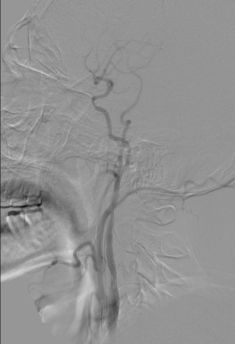

诊断分析 右侧颈内动脉C1段闭塞合并右侧大脑中动脉M1段闭塞。拟行支架机械取栓治疗。 治疗情况 耗材:8F血管鞘,8F导引导管,Navien 5F颅内支撑导管,Rebar-18微导管,0.014微导丝,Solitaire 4-20支架,SpiderFX保护伞,5-40球囊、1.5-20球囊,2-20球囊,9-40 Protégé。 支架: 1. 开通右侧颈内动脉C1: 通过1.5以及2.0球囊对C1段依次进行扩张,可见C1重度狭窄。

5mm Spider保护伞到位。

通过5.0mmX40mm球囊扩张C1段,恢复颈内动脉血流。